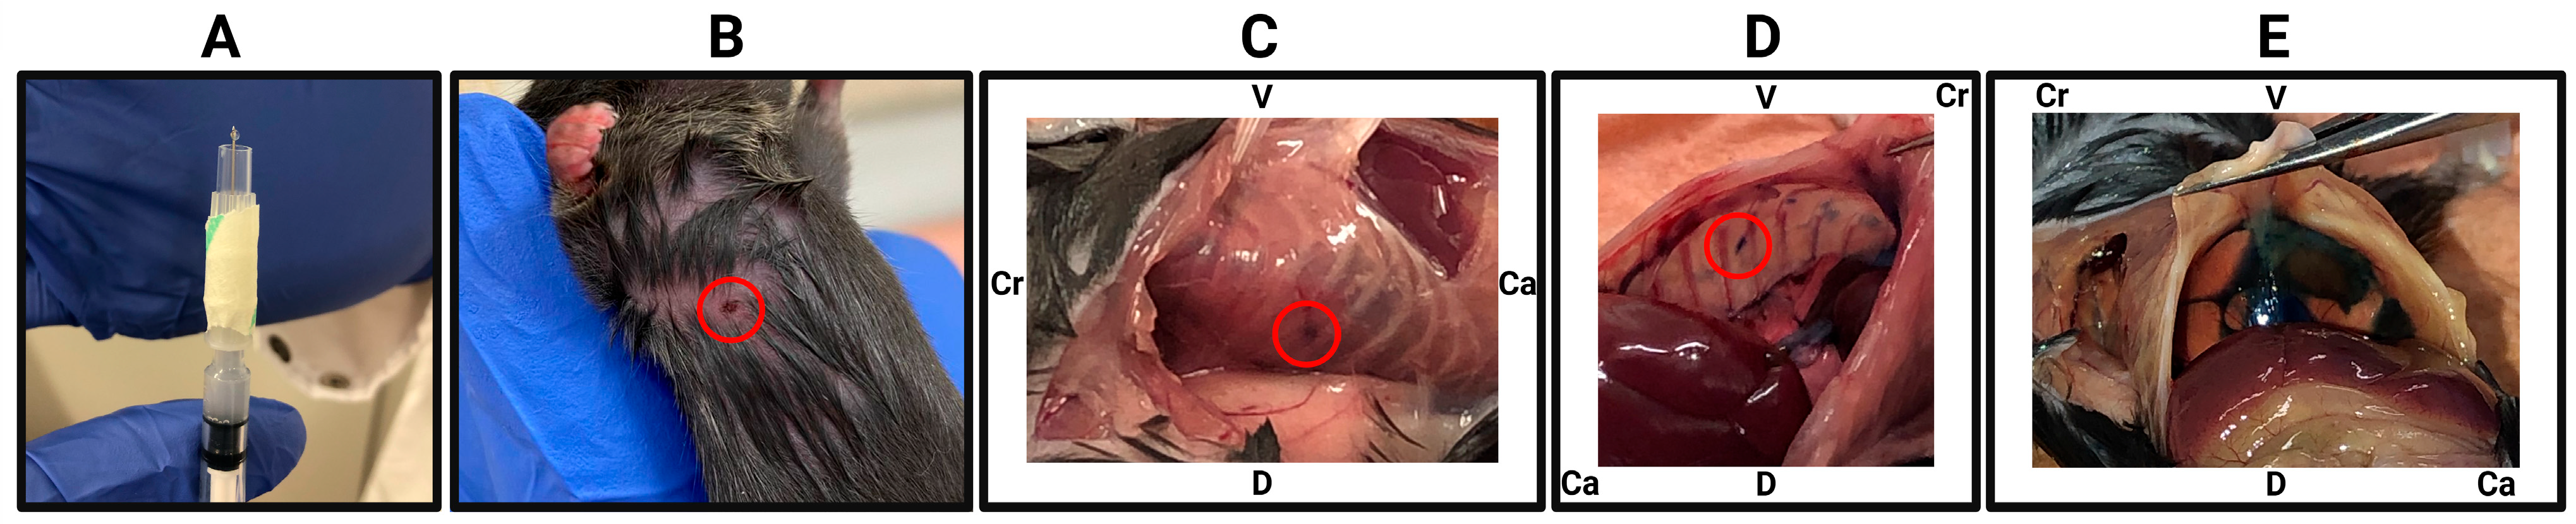

3.5. Pleural Fluid Collection

- To collect pleural fluid, the animal must lay flat on its back after euthanasia and four paws should be pinned to the work surface area.

- Make a small transverse incision, approximately 1 cm, on the abdomen using a sharp pair of scissors followed by a vertical anterior incision along the midline up to the top of the mediastinum. Open the skin from both sides. Then perform similar transverse incision in the peritoneal wall. The anterior incision of the peritoneal wall should only be large enough to expose the liver/stomach. It is very important to keep the pleural cavity intact at this stage.

- Using a pair of tweezers, carefully move back the liver to expose the entire diaphragm and visualise the effusion.

- Carefully insert a 25 G needle into the pleural space through the diaphragm, where the effusion has accumulated. Gently collect the fluid in a syringe (the needle might need to be repositioned at times). The fluid can then be transferred into an appropriate tube and stored accordingly for further analysis.

- OPTIONAL STEP: If little or no spontaneous effusion is present, the user may wish to perform a lavage, which can be performed with up to 1 mL of balanced salt solution or standard tissue culture media. Perform steps 1 to 4 as described above by injecting the desired solution into the closed chest cavity through the diaphragm prior to withdrawing the fluid through the same injection site.

3.6. Tumour Collection

- After collecting pleural fluid, circumferentially dissect the diaphragm to detach it. Carefully inspect the diaphragm and collect any tumours growing on its surface.

- Perform a median sternotomy by cutting along both sides of the sternum and removing it. This exposes the heart, lungs, and thymus. Inspect the thoracic cavity thoroughly for tumours, which may be present on the chest wall, lungs, heart, thymus, or diaphragm. Tumours typically appear light in colour, smooth or slightly nodular, and firm.

- Excise all visible tumours and process them for embedding and further histological analysis as required.